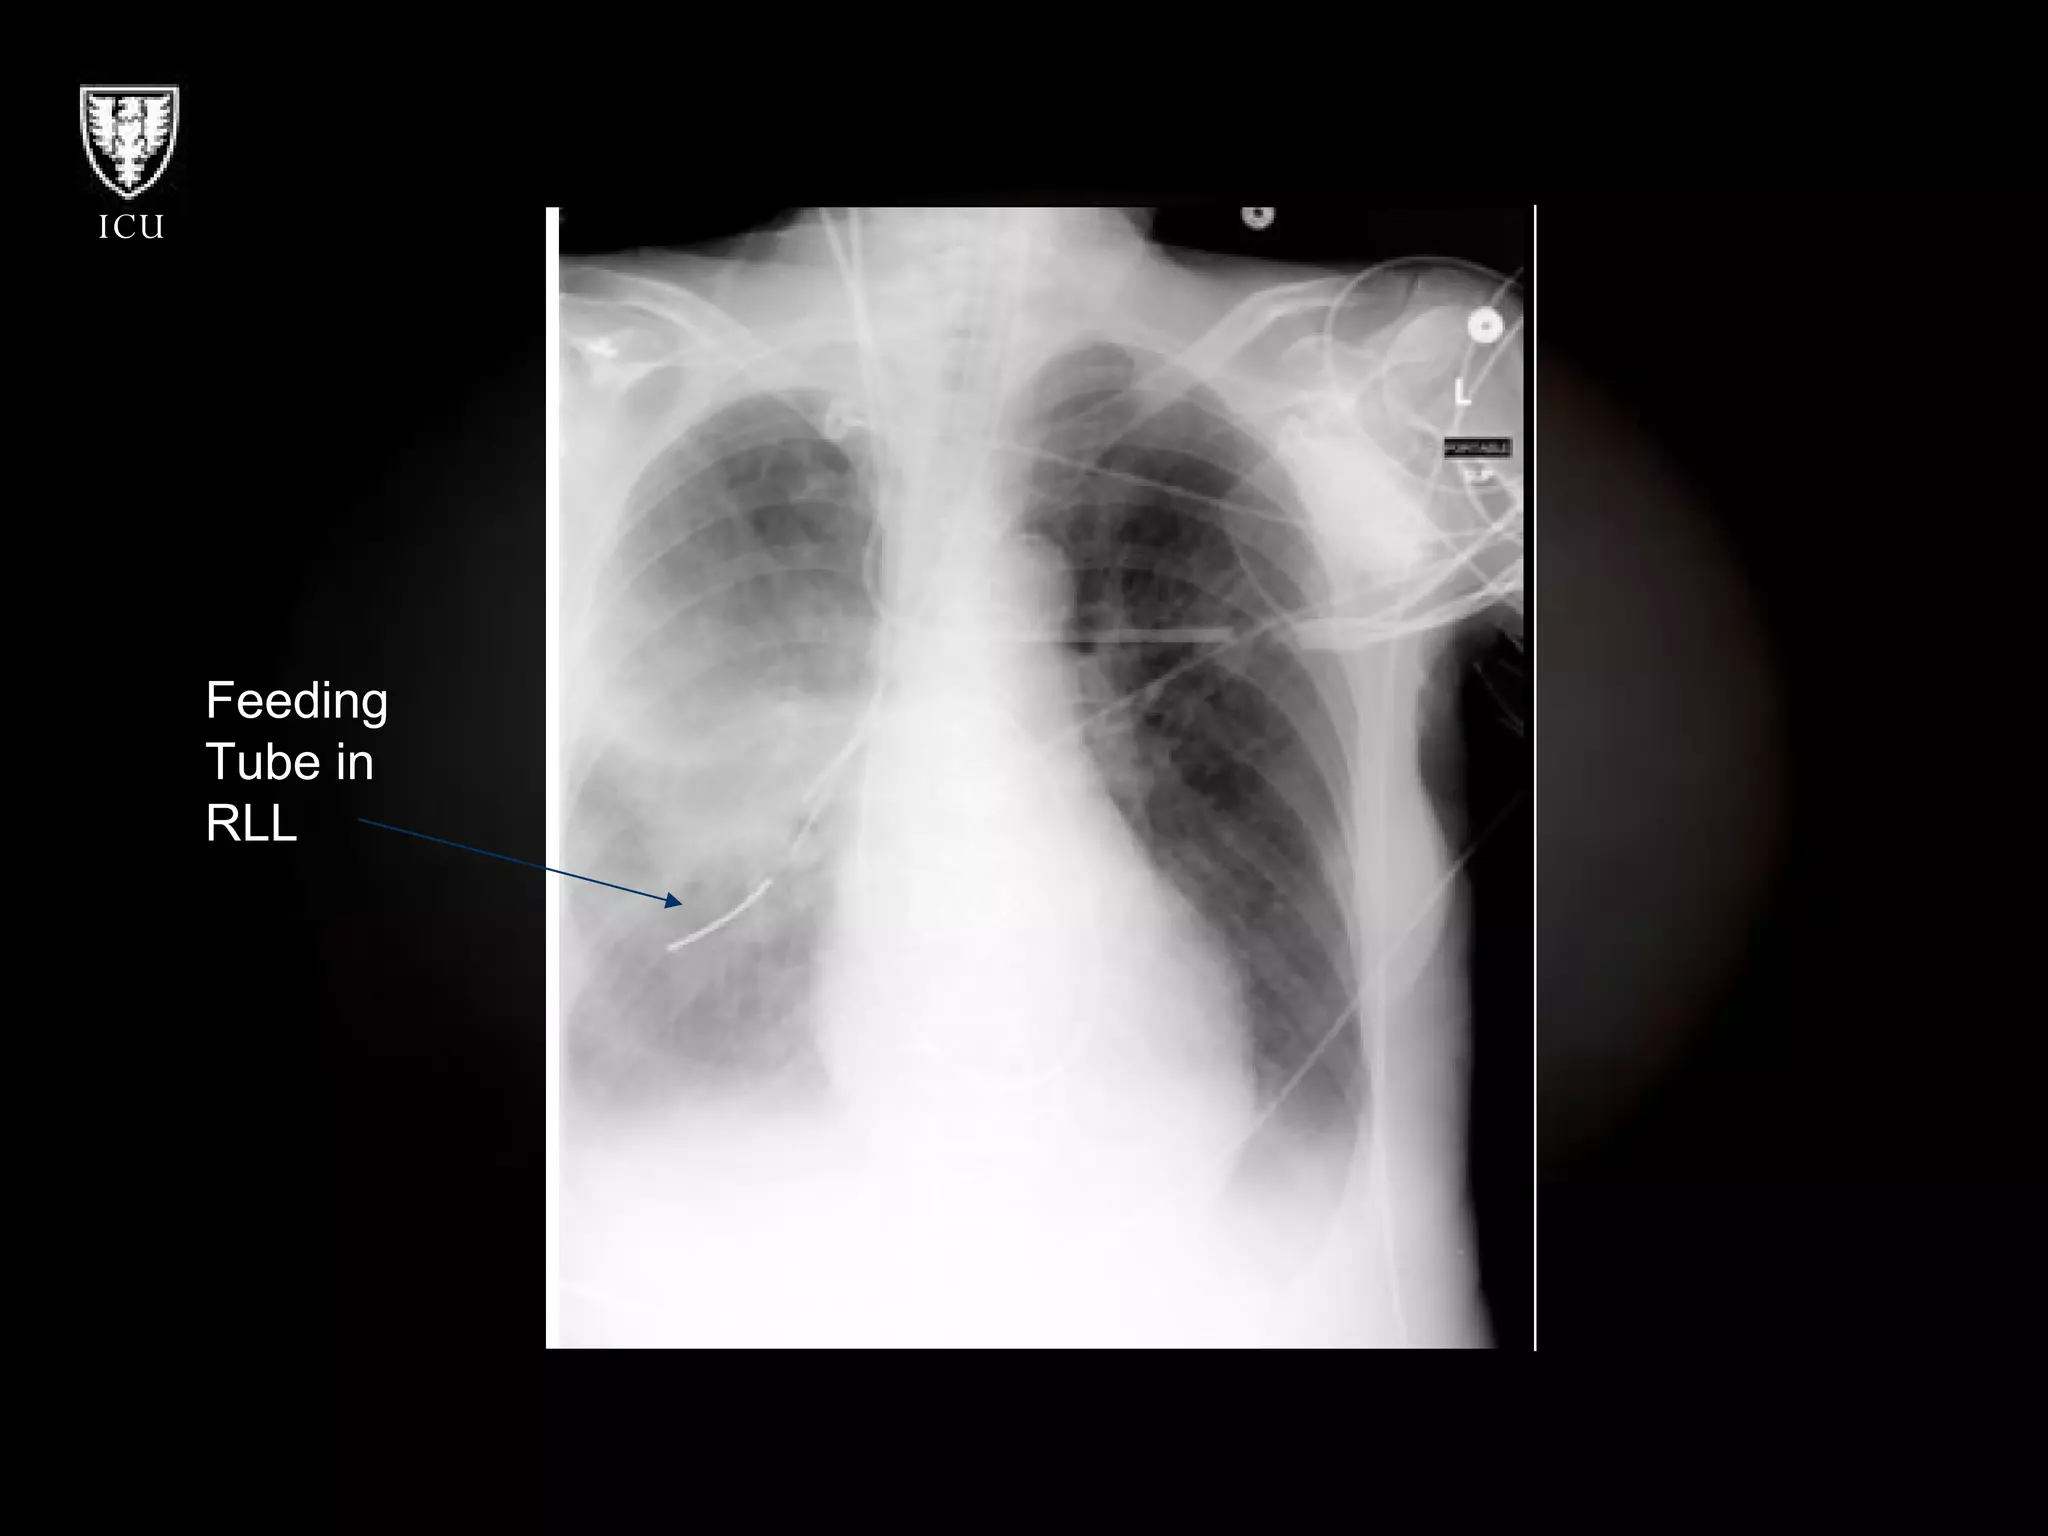

Feeding tube in lung

Feeding  Tube in  RLL